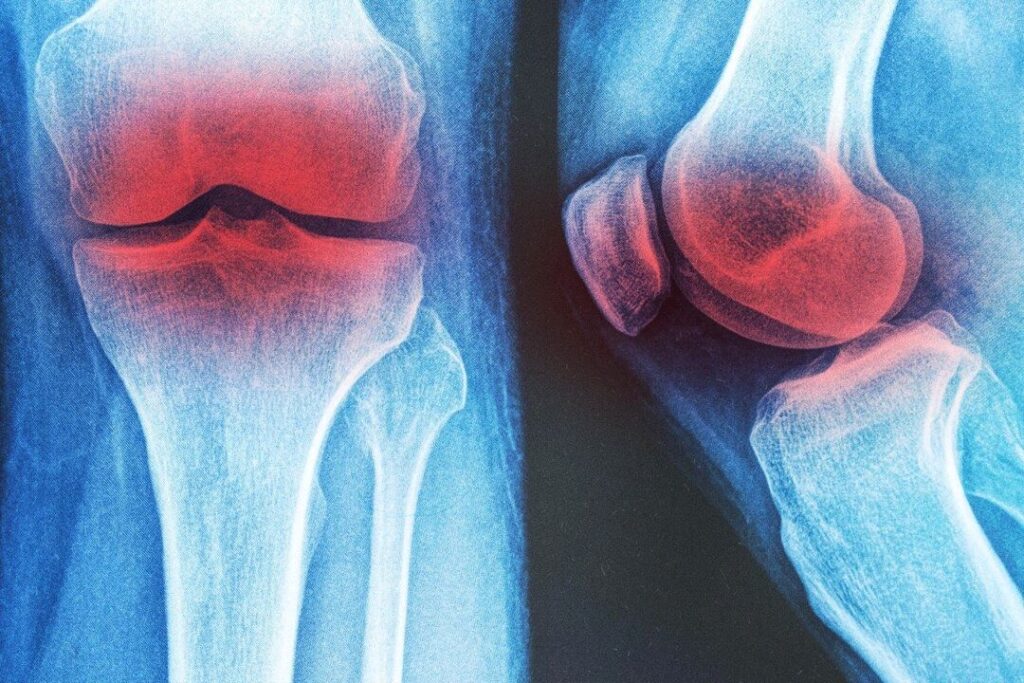

膝の変形性関節症に効く 3つの非薬物療法

膝の変形性関節症の痛みは薬だけに頼らなくても改善可能。研究が示す効果的な3つの非薬物療法とは?

ハイヒールの長期着用 ひざ関節症をもたらす=米研究

【大紀元日本8月17日】米オハイオ州立大学の研究チームは1日、ハイヒールを長期間履き続けるとひざに負担がかかり、くるぶしの機能を低下させ、変形性ひざ関節症に罹る可能性が大きくなると発表した。この研究